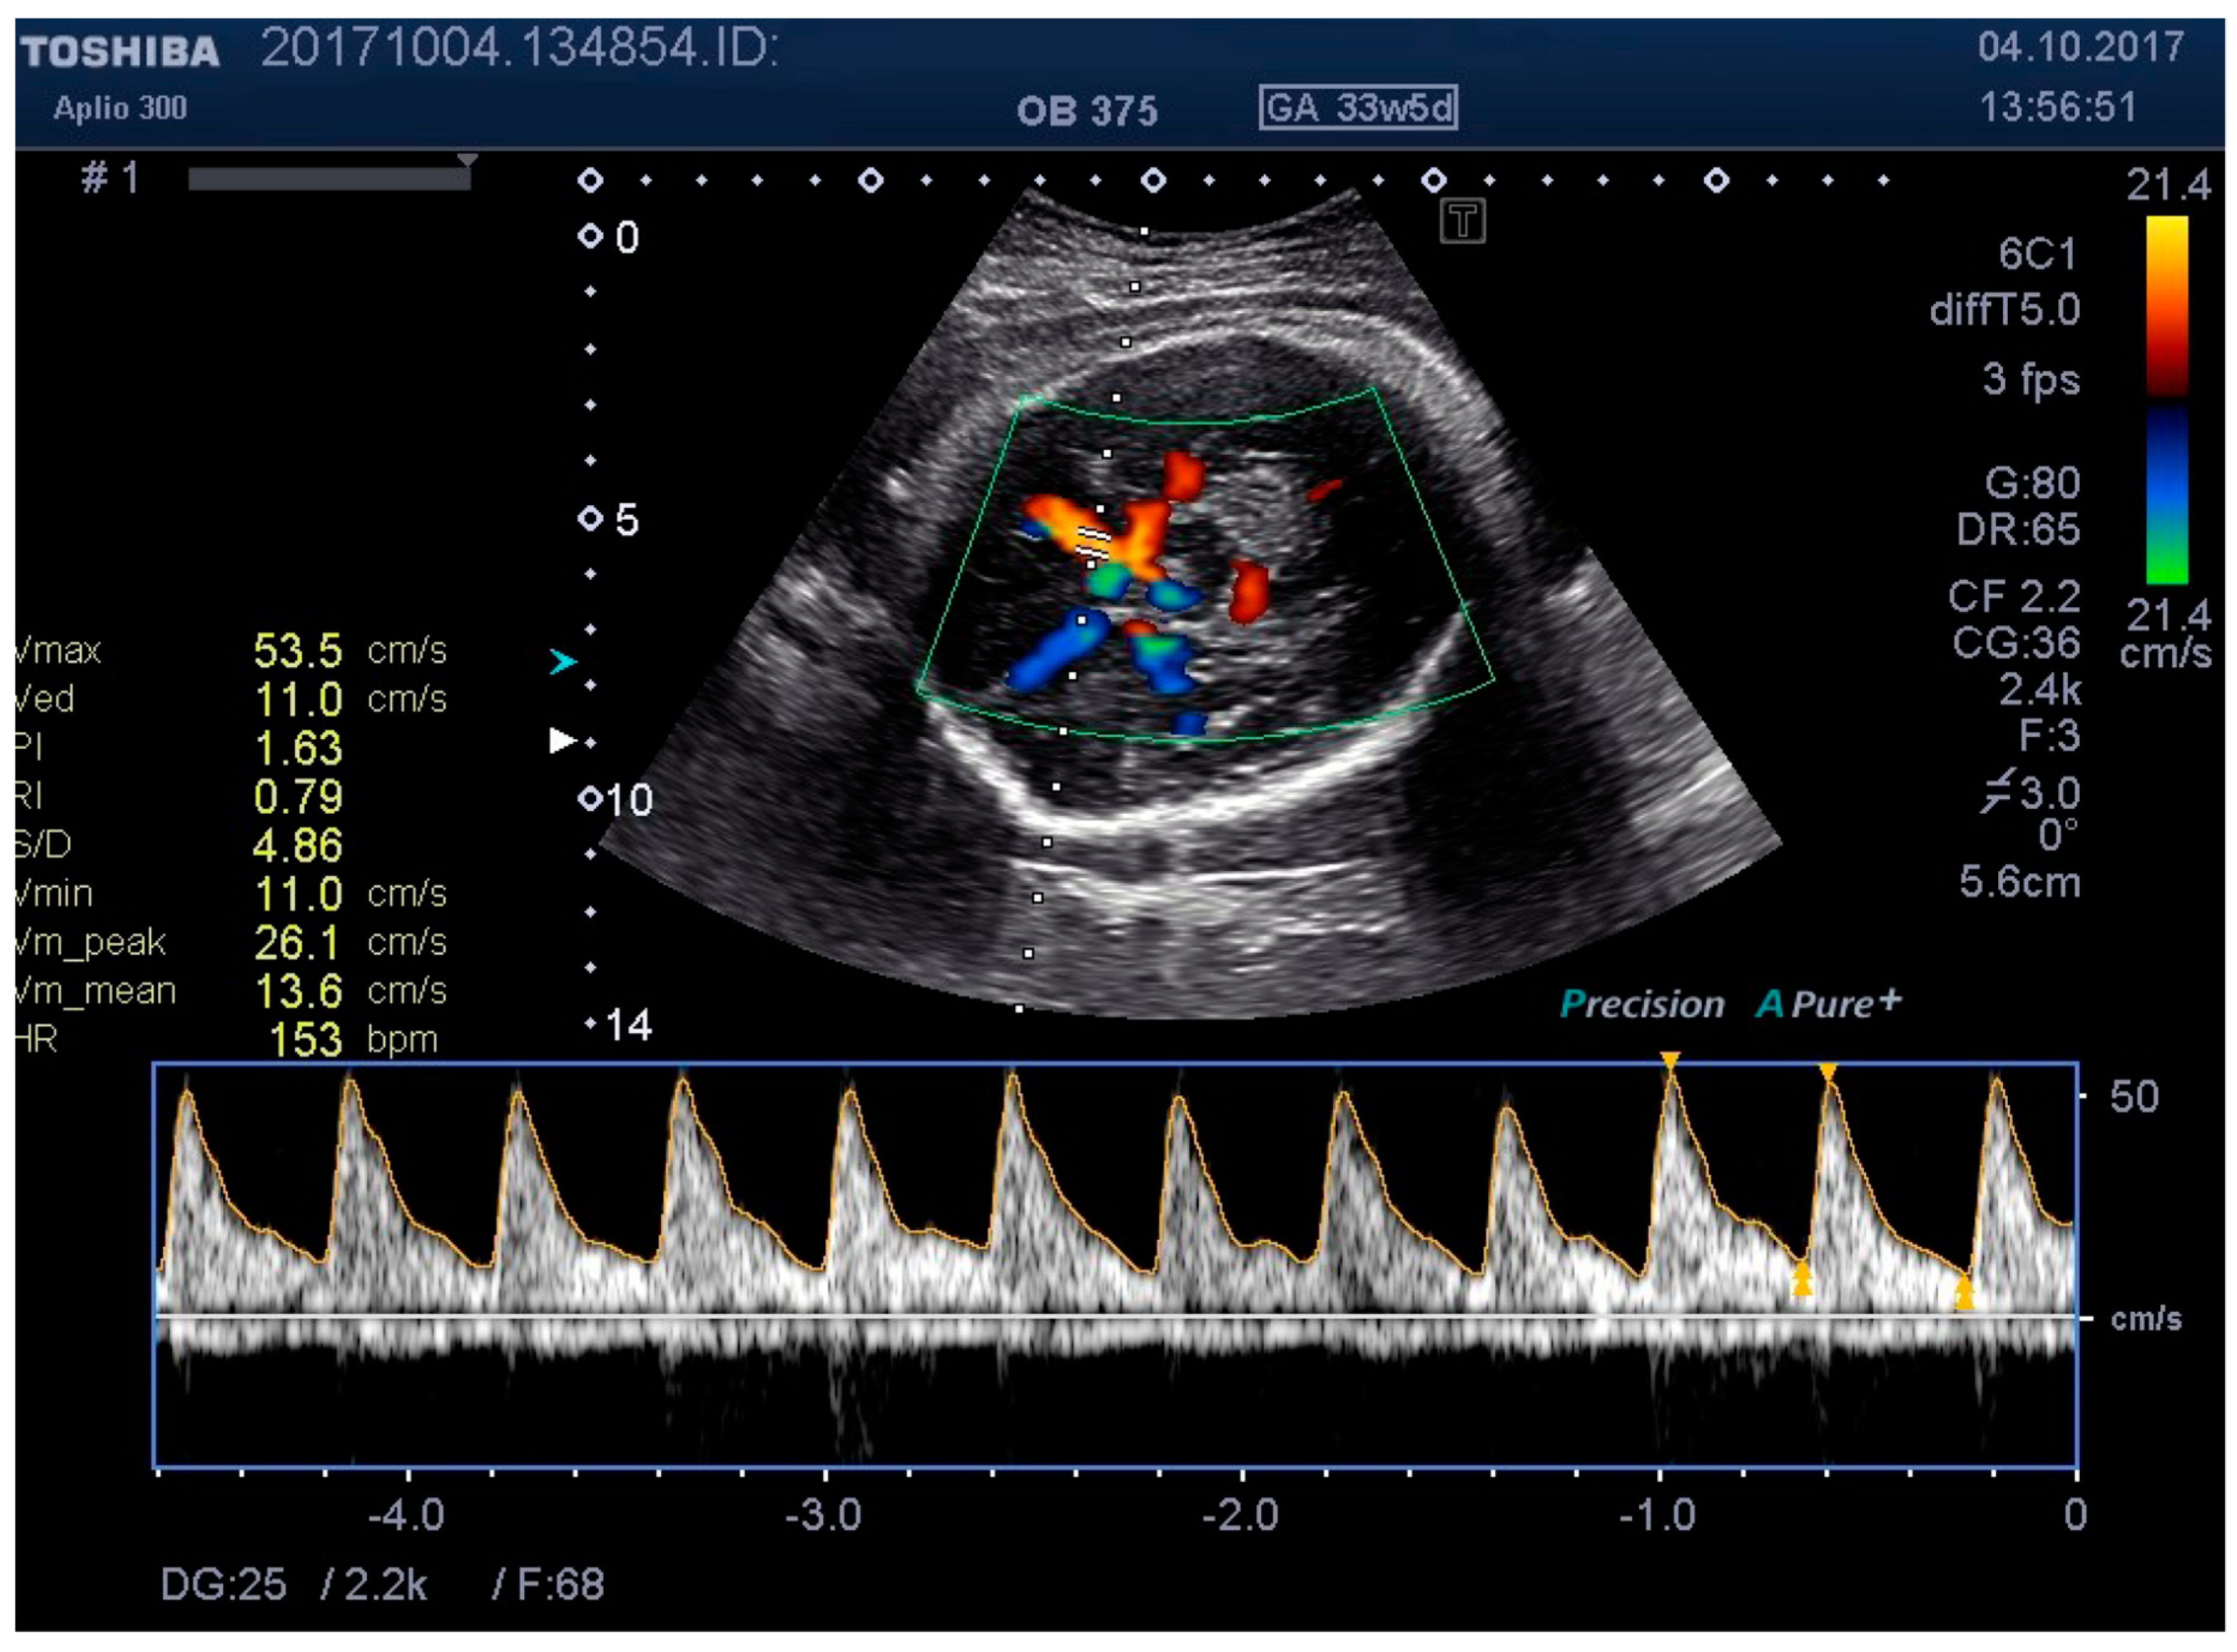

Figure 6. MCA Doppler spectrum with level 2 pressure.